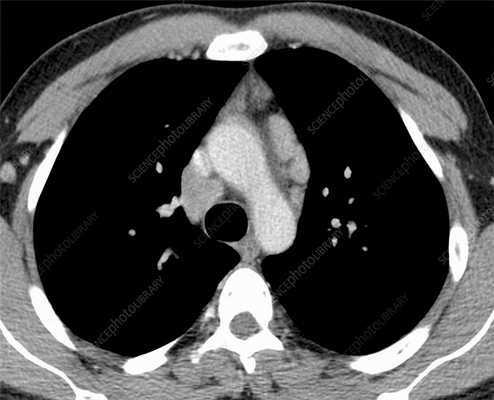

Первично диссеминированные заболевания легких выявляются по результатам аппаратных медицинских обследований (КТ, рентген). На посрезовой компьютерной томографии легких (МСКТ) в высоком разрешении очаги диссеминации и фиброза визуализируются лучше всего. Врач-рентгенолог может оценить объем поврежденной легочной ткани, выявить фиброзные тяжи (соединительнотканные спайки и рубцы), скопление жидкости и(или) гноя в альвеолярных пузырьках, сопутствующие патологии дыхательных путей, артерий, лимфатической системы.

Диссеминация представляет собой множественные патологические очаги (уплотнения) диаметром 1-10 мм. На КТ-сканах они выглядят как светлые пятна, в то время как в норме легочная ткань визуализируется практически однородным темным цветом. Очаги могут быть абсолютно разными по размеру, форме (эллипсообразные, с неровными краями) и морфологии. Нередко вокруг очагов обнаруживается перифокальное воспаление. Они могут сливаться и в таком случае напоминают инфильтративные процессы при пневмонии. Диссеминация также проявляется в виде очаговых микро повреждений с кровью и отеками.

Гранулематозы и диффузно расположенные «матовые стекла» на КТ не являются специфическим признаком туберкулеза. Первые обнаруживаются и при саркоидозе, а вторые — при пневмониях и других заболеваниях.

Пневмокониоз тоже носит гранулематозный характер. На КТ-сканах отчетливо видны множественные узелковые уплотнения разной плотности. Такие уплотнения следует проверять на предмет того, является ли процесс доброкачественным, нет ли онкологической угрозы.

Саркоидоз легких - это онкологическое заболевание. Его основными признаками на КТ являются диссеминация и медиастинальная лимфаденопатия. Диссеминация на сканах выражена не так ярко как при прогрессирующем туберкулезе, однако определенное сходство есть. Диагностику затрудняет легочный фиброз. Вместе с дессиминированнным поражением дыхательного органа присутствуют васкулиты, периваскулиты, перибронхит.

Лимфома легких на КТ

Признаки лимфомы легких особенно выражены на четвертой стадии заболевания, когда болезнь поражает дыхательный орган. На КТ при этом будут видны увеличенные лимфоузлы, формирующие цепочки, конгломераты. При этом у пациента может также наблюдаться отек легких. Однако высокая разрешающая способность КТ позволяет выявить лимфому на ранней, первой стадии.

На КТ лимфомы, как и любые уплотнения, визуализируются сравнительно более светлым цветом. В норме воздушная легочная паренхима практически однородного темного цвета. Иногда таких уплотнений несколько и они диссеминированны. Контуры лимфомы четкие и ровные. Вокруг патологических очагов обнаруживаются участки «матового стекла».